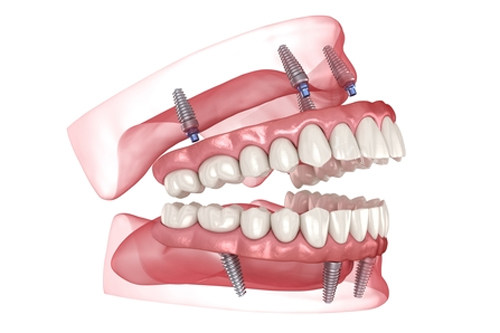

全口种6颗牙需要5万?

以“种6颗牙改善全口咀嚼”的All-on-6技术为例,其总费用因植体品牌、材质及附加手术差异,价格跨度从3万元至15万元不等。本文结合国内口腔医院报价与临床实例,揭秘不同植体材料收费逻辑,助你避开价格陷阱。

一、全口种植牙价格构成:植体≠总费用

全口种植牙费用主要由植体、牙冠、医疗服务及附加手术四部分构成,部分机构通过拆分收费变相加价: